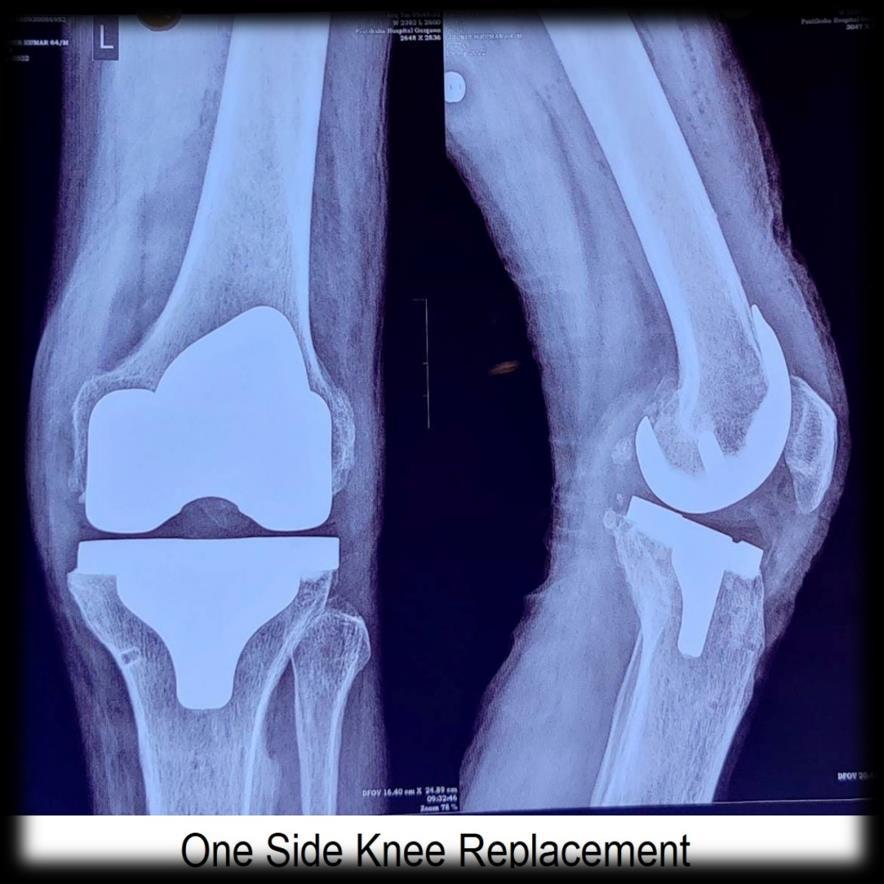

Two sides Knee Replacement

The bilateral procedures had a significantly higher rate of complications than unilateral procedures, almost entirely because of thromboembolic problems. The studies have shown Bilateral TKA had an increased risk for all complication when compared with unilateral TKA regardless of health status. A greater than fourfold increase for the second and third quartiles, and a greater than threefold increase for the fourth quartile (least healthy patients. Therefore, we recommend simultaneous bilateral knee arthroplasty only for patients in ASA classes 1 and 2.